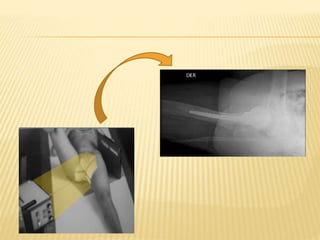

La paciente sufrió una fractura de cadera en un accidente y fue llevada a un servicio de urgencias donde se diagnosticó la lesión a través de una radiografía simple. Posteriormente fue operada para fijar la fractura y luego de la cirugía se le realizaron nuevas radiografías para control, cuyo resultado fue informado por el médico radiólogo. Finalmente, luego de pasar un tiempo en reposo hospitalizada, la paciente se recuperó completamente y recibió el alta.